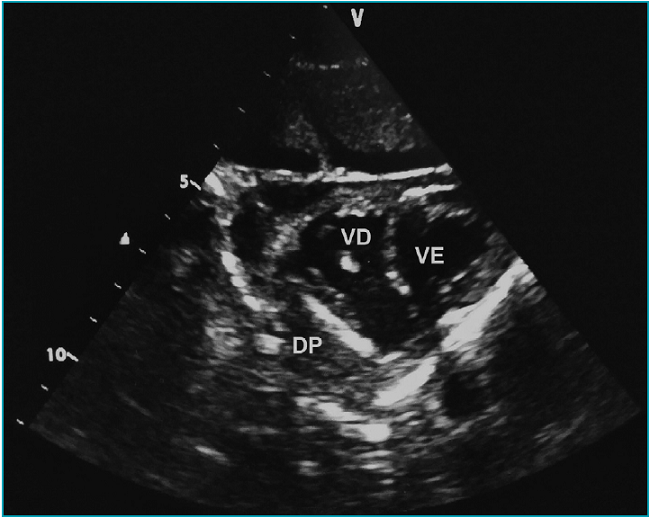

Após estabilização hemodinâmica, foram realizadas tomografia computadorizada (TC), punção lombar, radiografia, hemoculturas e exames laboratoriais. O hemograma inicial foi: Hb 6,1 g/dL; Ht 19,8%; contagem de glóbulos vermelhos 3.320.000/mm3; contagem de glóbulos brancos 4.290/mm3 (15,3% de neutrófilos; 12,2% de células em banda; 70,4% de linfócitos; 2,1% de monócitos); contagem de plaquetas 166.000/mm3. Análise do líquido cefalorraquidiano (LCR) revelou: proteínas 1.291 mg/dL; hemácias 730/mm3; glicose 0 mg/dL; leucócitos 51 células/mm3 (86% de neutrófilos). Numerosos cocos gram-positivos foram encontrados na bacterioscopia do LCR. Foi administrado ceftriaxona à paciente na dose de 100 mg/kg. Para estabilização hemodinâmica, foi necessária infusão de epinefrina na taxa de 0,3 mcg/kg/min. TC revelou edema cerebral difuso e radiografia de tórax mostrou discreta opacidade heterogênea peribrônquica no hemitórax direito e cardiomegalia. Ultrassonografia à beira do leito revelou derrame pericárdico septado (Figura 2), sem consolidação pulmonar. O exame neurológico foi compatível com morte encefálica e não foi realizada pericardiocentese. Streptococcus pneumoniae foi identificado no sangue e nas culturas de LCR. As bactérias eram suscetíveis aos seguintes antibióticos: sulfametoxazol trimetoprim, benzilpenicilina, eritromicina, ceftriaxona, vancomicina e levofloxacina. A morte cerebral foi confirmada de acordo com o protocolo.6

A pericardite purulenta é diagnosticada quando o conteúdo purulento é drenado do espaço pericárdico ou quando há cultura positiva de bactérias a partir do líquido pericárdico.11 A tríade clássica de sintomas, descrita por Claude Beck em 1935 (hipotensão, distensão jugular e abafamento de bulhas cardíacas) é observada em até 40% dos casos.12 A elevação do segmento ST é uma característica eletrocardiográfica clássica da pericardite, mas raramente encontrada no tipo purulento.10 A maioria dos casos descritos teve diminuição da amplitude ou ausência de alterações no segmento ST. Ecocardiografia e TC também podem ajudar no diagnóstico. A ecocardiografia pode ser realizada à beira do leito, sem radiação ionizante, e com baixo custo, além de ser capaz de revelar múltiplos sinais de tamponamento cardíaco e identificar o local mais adequado para pericardiocentese. Embora não tenha sido realizada análise do líquido pericárdico no caso relatado, bandas e loculações foram visualizadas no mesmo por meio da ecocardiografia. Tais achados ultrassonográficos são sugestivos de pericardite purulenta no paciente séptico.13